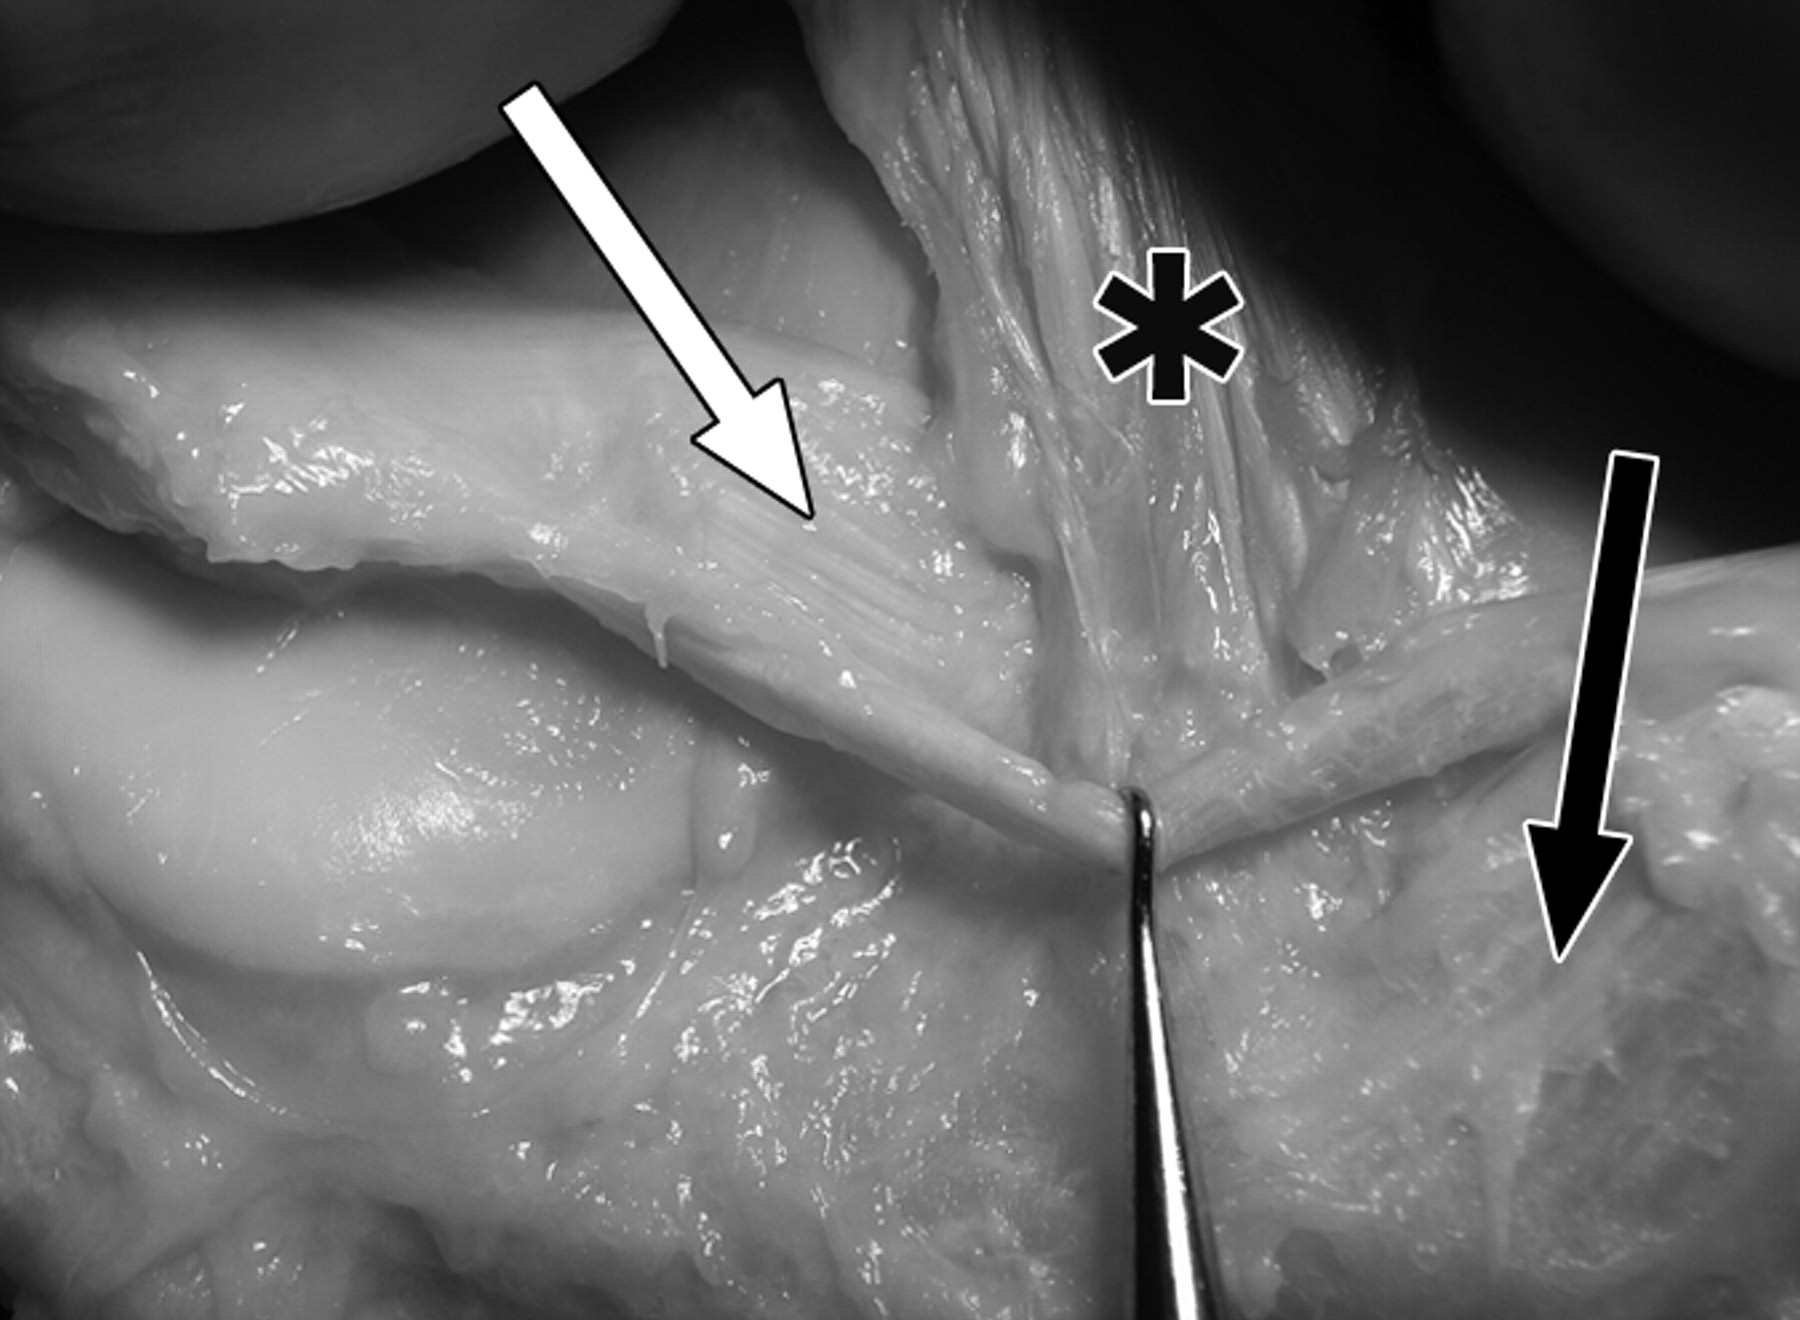

59岁男性大体标本。

照片显示了膝前根、膝横韧带和前交叉韧带胫骨止点的解剖关系。膝关节前视图,切除半月板和韧带,显示内侧半月板前根(黑色箭头)在前髁间嵴(箭头)、外侧半月板前根(白色箭头)和ACL胫骨插入部位(星号)上的轮廓。LP =外侧胫骨平台,LT =外侧胫骨结节,MP =内侧胫骨平台,MT =内侧胫骨结节。

照片显示了膝前根、膝横韧带和前交叉韧带胫骨止点的解剖关系。膝关节前视图,半月板和韧带就位,显示内侧半月板前根(黑色箭头)、外侧半月板前根(白色箭头)、ACL(星号)和膝横韧带(钩)的关系。

照片显示了膝前根、膝横韧带和前交叉韧带胫骨止点的解剖关系。前交叉韧带切除后的膝关节前视图(星号)显示外侧半月板前根(白色箭头)和内侧半月板前根纤维(黑色箭头)的共同插入。